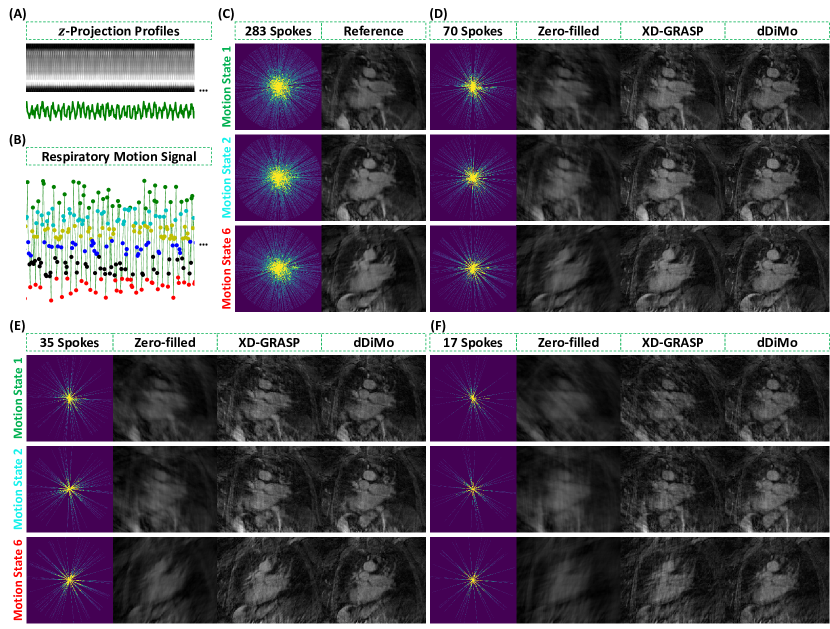

Figure 7 presents a qualitative comparison of lung reconstructions with 70, 35, and 17 spokes across motion states using Zero-filled, XD-GRASP, and the proposed dDiMo method. Reconstructions are shown for representative motion states (Motion State 1, Motion State 2, and Motion State 6), highlighting the effectiveness of each method in handling undersampled dynamic lung imaging. Zero-filled reconstructions exhibit severe artifacts and significant loss of structural detail, particularly in motion-affected regions. For instance, Motion State 1 demonstrates extensive blurring and cannot delineate key anatomical features. XD-GRASP reduces artifacts and partially restores structural details compared to Zero-filled; however, residual blurring, missing subtle textures, and noise remain apparent, especially at higher undersampling levels (e.g., 17 spokes). In contrast, dDiMo achieves superior performance across all motion states by effectively suppressing artifacts, recovering fine structural details, and maintaining consistency across motion states. In the most challenging scenario, with 17 spokes, dDiMo reconstructs most of the structural details, producing sharper boundaries and enhanced structural integrity across respiratory phases. These qualitative results highlight the advantages of the proposed dDiMo method over traditional approaches, demonstrating its capacity to restore structural details and improve motion-resolved reconstructions.